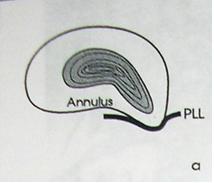

Развитие грыж характеризуется определенной стадийностью:

I стадия — протрузия диска — смещение в сторону позвоночного канала пульпозного ядра и выбухание в позвоночный канал элементов фиброзного кольца межпозвонкового диска без нарушения целостности последнего;